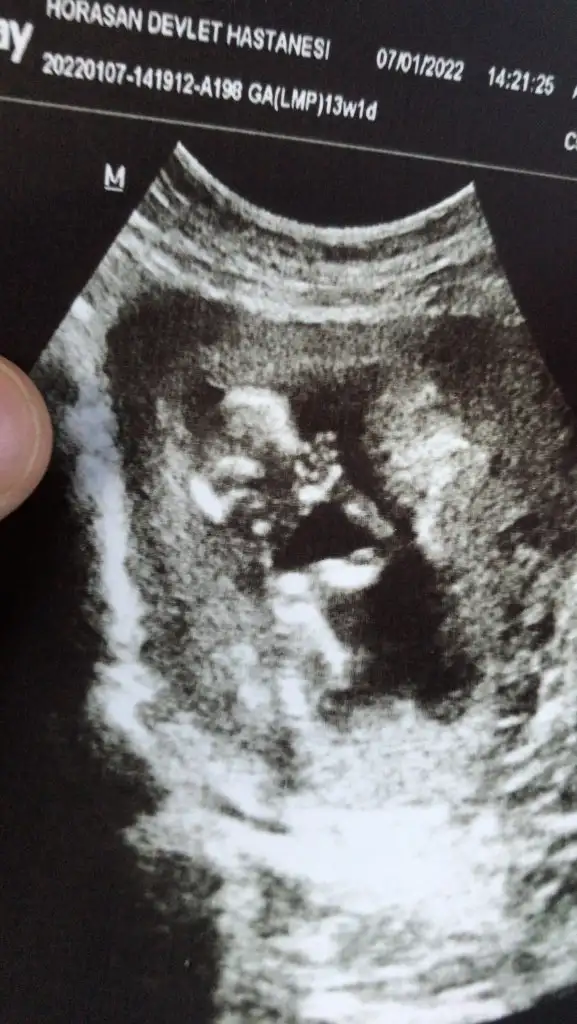

Erkek gibiCinsiyet ne bakabilir misiniz?Ikra meyra

Erkek gibi sankiBuna da bakar mısınız 12+6Ikra meyra

Çok teşekkür ederim vakit ayırıp baktığınız için 1 ay sonrasına gün attı doktorum kesinlesir kesinlesmez paylasicamKiz görünüyor